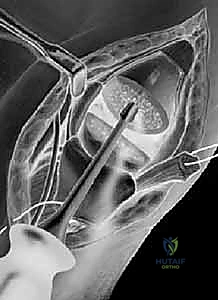

الخيارات الجراحية المتقدمة مع الأستاذ الدكتور محمد هطيف

تتعدد التقنيات الجراحية، ويتم اختيار التقنية الأنسب بناءً على عمر المريض، مستوى نشاطه، ومرحلة المرض. يُعد الدكتور هطيف رائداً في تقديم هذه التقنيات العالمية في غرف العمليات في صنعاء، مجهزاً بأحدث أدوات الجراحة المجهرية والمناظير.

1. استئصال العظم المربعي مع إعادة بناء الأربطة (Trapeziectomy with LRTI)

تُعد هذه العملية "المعيار الذهبي" (Gold Standard) والأكثر شيوعاً ونجاحاً عالمياً لعلاج هذه الحالة.

جراحة استئصال العظم المربعي وإعادة بناء الأربطة LRTI

• آلية العملية: يقوم الجراح بإزالة "العظم المربعي" (Trapezium) بالكامل، وهو العظم الذي يسبب الاحتكاك المؤلم. بمجرد إزالته، يختفي الألم تماماً لأنه لم يعد هناك عظم يحتك بعظم.

• **إعادة بناء الأربطة (LRTI):